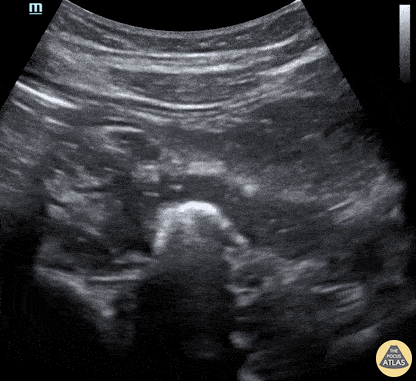

Small bowel obstruction showing a transition point in the ileum. Steven Johnson @alittlecoldgel